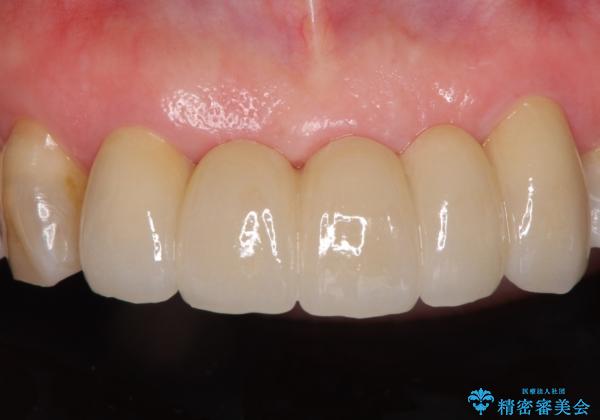

装着されていたブリッジは、支台となっている歯と欠損している歯で色が大きく異なっていましたが、オールセラミックとしたことで、全体的に色調の整った仕上がりとなりました。

歯肉ラインがきれいに整い、患者様には大変満足していただきました。